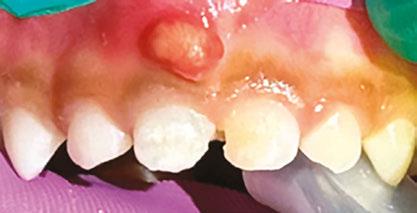

Several clinical solutions exist for primary anterior teeth with multisurface decay. Full coronal restoration of carious primary incisors may be indicated when caries is present on multiple surfaces, pulpal therapy is indicated, caries may be minor, but oral hygiene is very poor, or in a child with severe early childhood caries or a high caries risk diagnosis.1 Depending on the clinical scenario, a minimally invasive approach with the utilization of a high viscosity glass ionomer cement (HVGIC), with or without the combination of silver diamine fluoride (SDF) in a strip crown form, may pause the caries progression and provide an adequate clinical solution. Resin composite strip crowns have shown 80% retention rates and adequate parental satisfaction,1-4 although composite resin strip crowns have shown lower retention rates in teeth with decay involving three or more surfaces and particularly in children with a high caries risk4-6 (Figure 1). This could be from the continued high caries risk behaviors of the patient, as composite resin strip crowns in this population have shown to have increased inflamed marginal gingiva and gingival bleeding, increased plaque retention along the restoration, and loss of some restorative material.5,6

2: NuSmile® Anterior Zirconia crowns at 2-year follow up. Note the high amount of plaque accumulations along the untreated cuspid and existing stainless-steel crowns

A 2-year-old male who received full mouth dental rehabilitation (FMDR) under general anesthesia presented for his 6-month recall at 2-year post FMDR. He had significant plaque accumulations with poor oral hygiene along his existing stainless-steel crowns (SSCs) and non-treated teeth. Additionally, the patient had gingival bleeding and gingival inflammation

around these clinical sites. His anterior zirconia crowns showed healthy gingival margins with little-to-no plaque accumulations. This positive clinical finding is from the highly polished nature and biocompatibility of pediatric zirconia crowns. These restoration features limit plaque accumulations on the restoration and along the marginal gingiva, providing a localized positive aspect directly related to the choice of restorative material (Figure 2).

Case 2

A 3-year-old female presented with pulpal necrosis and abscess on #E and pulpal necrosis on #F. Extraction therapy or pulpectomy was offered. The family was highly motivated to retain #E and #F. The pulpectomy was performed with 0.02 K-Flex hand files, 3% NaOCl with a lateral vented needle, obturated with Vitapex (Neo Dental International Inc., Federal Way, Washington), a premixed paste of calcium hydroxide and iodoform. The access was filled with a HVGIC sealing the pulp therapy and increasing the clinical success by minimizing the potential for bacterial contamination. NuSmile ZR anterior crowns were selected as offering a full-coverage, esthetic, cemented restoration with no polymerization shrinkage when compared to a composite restoration. Crowns were cemented with NuSmile® BioCem (NuSmile, Houston, Texas). This is clinically beneficial as the provider would want to cement a restoration that provides limited microleakage minimizing the potential for bacterial contamination.15-17 At 6-month follow up, lesion healing had occurred with healthy gingival margins and no plaque accumulations (Figure 3).

A 4-year-old female presented with existing Silver Modified Atraumatic Restorative Technique (SMART) style restorations on #D, #E, #F, #G, and caries on other teeth. These anterior lesions

had been previously treated using SDF and covered with a HVGIC in a strip crown form. Though her lesions were stable from the clinical success of the SDF and HVGIC, these restorations were starting to fracture and demonstrate loss of material. The family wanted a more esthetic treatment option that would have a longer survivability. Additionally due to her high caries risk nature, a full coverage restoration with NuSmile® ZR anterior crowns were a more ideal solution in stabilizing her extensive decay pattern and covering staining from SDF therapy (Figure 4).

Figure 3: NuSmile® ZR Crowns were selected as a cementable full coverage restoration. At 6-month recall, apical tissues were healed with excellent gingival health Figure 4: SMART style restorations that were definitively restored with NuSmile® ZR Crowns as an esthetic option to cover SDF staining